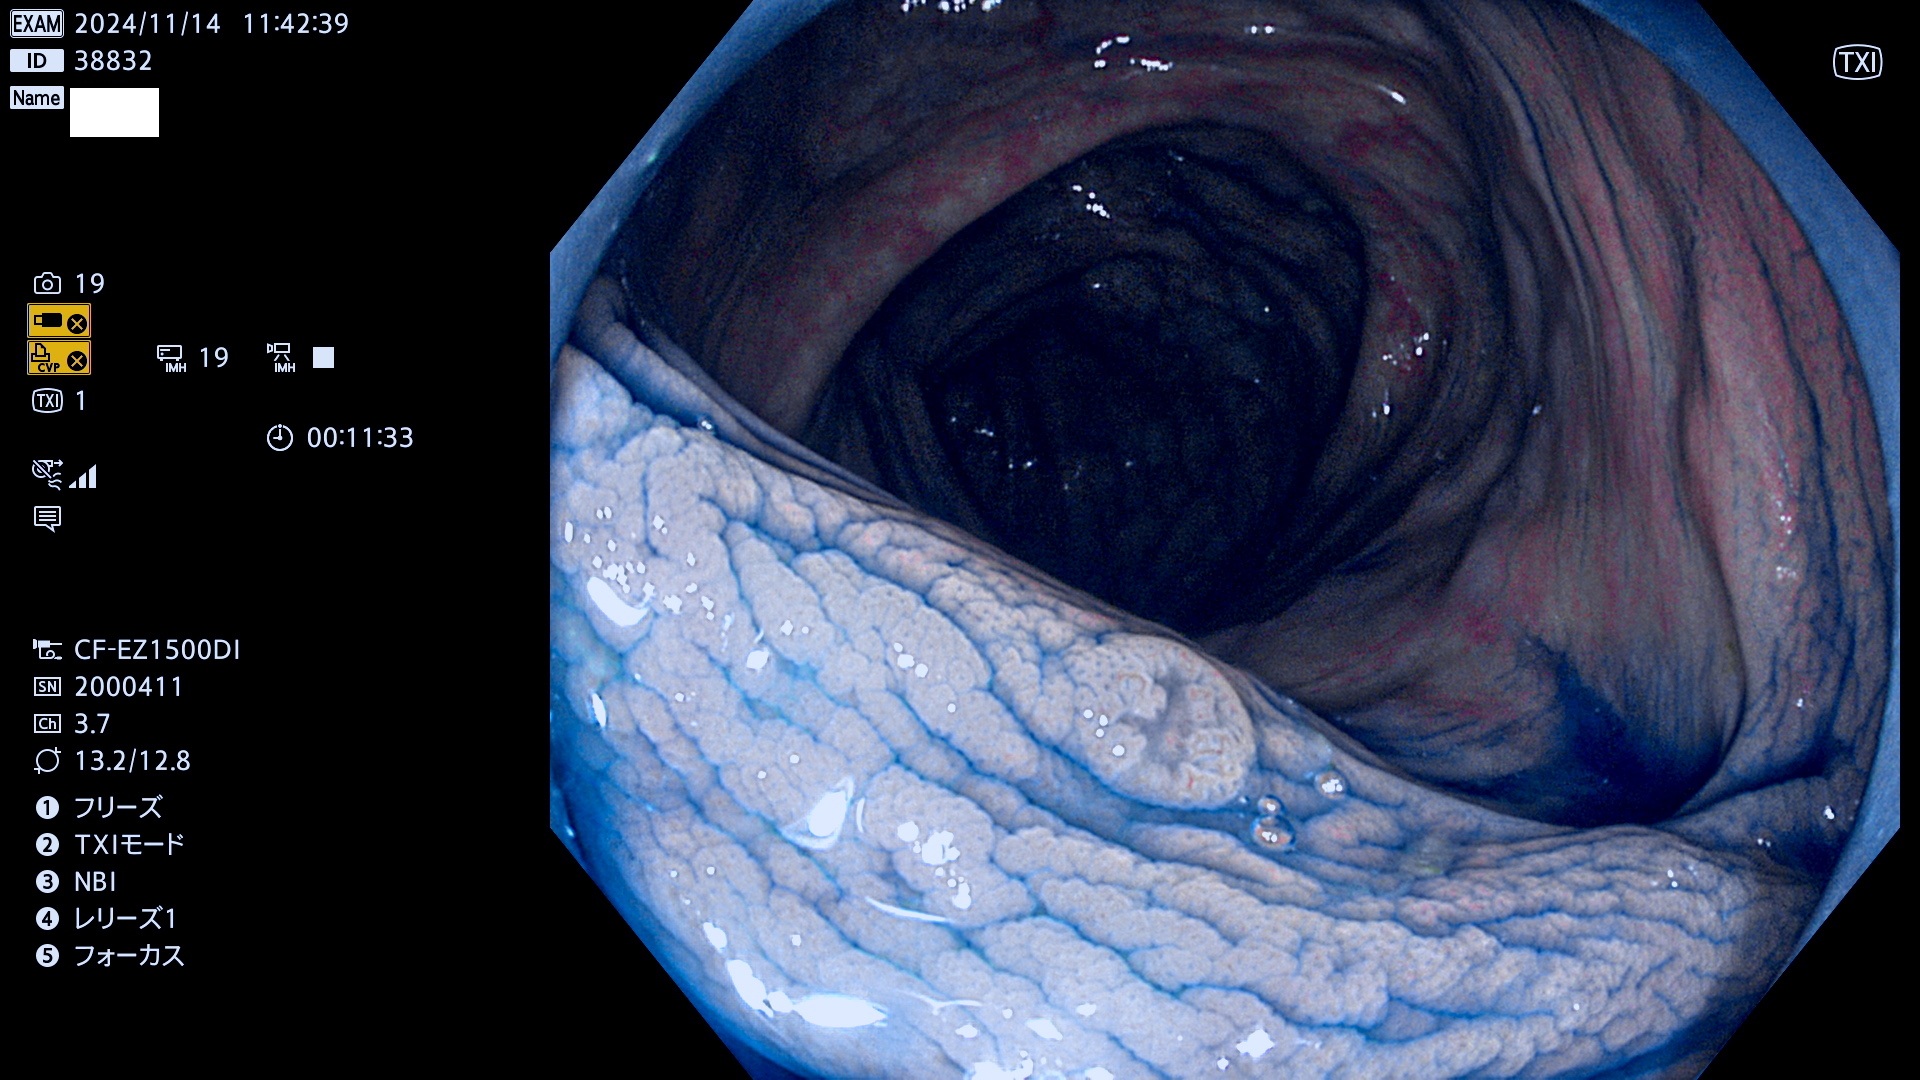

完全に平坦な物をUb、陥凹している物をUcと呼びます。最も発見が難しく危険な病変です。

毎週の検査(木・金・土・日)に発見されたUb、Uc型・腺腫を、その週の日曜の夜にUPし1週間、提示します。

抽出の対象期間 2024年11月14日〜11月17日の4日間(48件の検査)7件 (7/48=14%)